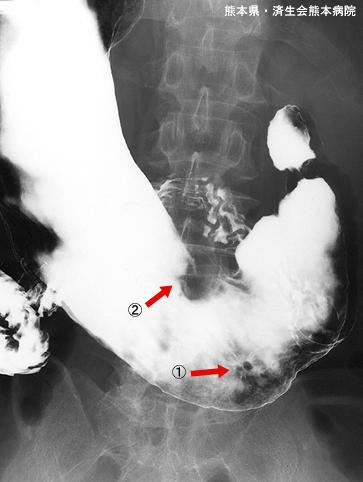

疾病(病理主体)的分类恶性上皮性肿瘤/腺癌

部位(按器官分)胃(部位)/体部

检查方法X线

肿瘤的肉眼分类0型(表在型)/IIc型(IIc)

肿瘤最大直径1~9

肿瘤的深度sm